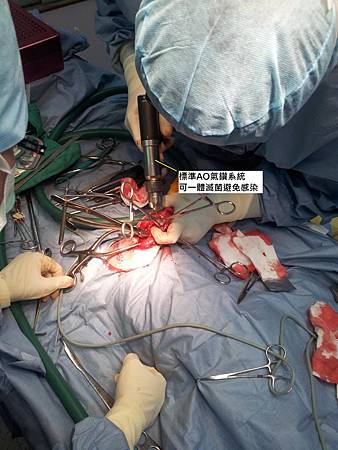

手術使用標準AO氣鑽系統配合AO鋼板實施骨盆整復手術,大腿骨折部分則使用鋼釘系統給予牢固的固定。

上圖,使用標準AO氣鑽系統,可一體滅菌避免感染。